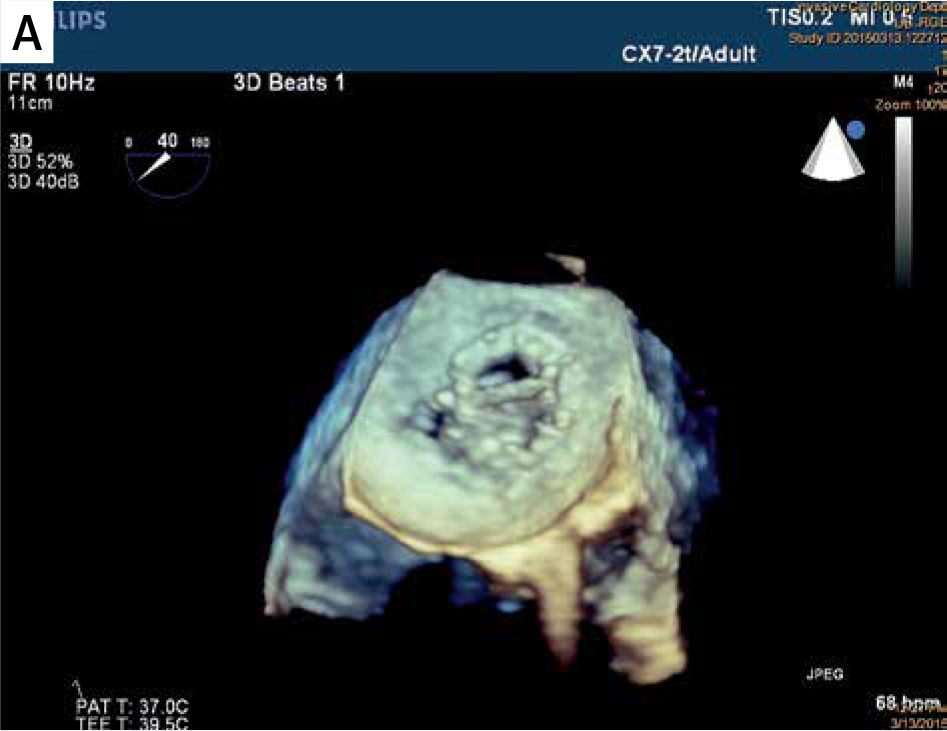

Zamknięcie przecieków zastawkowych metodą przezskórną stanowi duże wyzwanie kliniczne, szczególnie ze względu na złożoność anatomiczną kanałów PVL (ang. paravalvular leak – przecieków zastawkowych) oraz ryzyko kolizji okludera z mechanicznymi elementami zastawki. Zespół badawczy postawił sobie za cel ocenę możliwości wykorzystania danych z echokardiografii przezprzełykowej (3D-TEE) do stworzenia modeli 3D, które pozwoliłyby lepiej dobrać typ i rozmiar okludera przed zabiegiem.

Zespół z GCM i ŚUM wykorzystał dane z echokardiografii 3D-TEE, które po konwersji do plików 3D, dzięki segmentacji w oprogramowaniu powiązanym z drukarką 3D (slicer), zostały wydrukowane w rzeczywistej skali na drukarce Stratasys Objet 30 (v.3) w technologii PolyJet.

W projekcie przeanalizowano 8 przypadków pacjentów z PVL w mitralnych zastawkach mechanicznych lub biologicznych. W testach symulacyjnych przeprowadzonych na wydrukowanych modelach, dobrano optymalne rozmiary okluderów, co później porównano z rzeczywistym postępowaniem klinicznym.

W 7 z 8 przypadków dobór okludera na podstawie wydrukowanego modelu pokrywał się z decyzją podjętą w trakcie rzeczywistego zabiegu. W jednym przypadku konieczna była zmiana strategii, jednak model także wskazywał taką możliwość jako jedną z alternatyw.

- Segmentacja obejmowała wybór ramek rozkurczowych dla lepszej widoczności kanału PVL